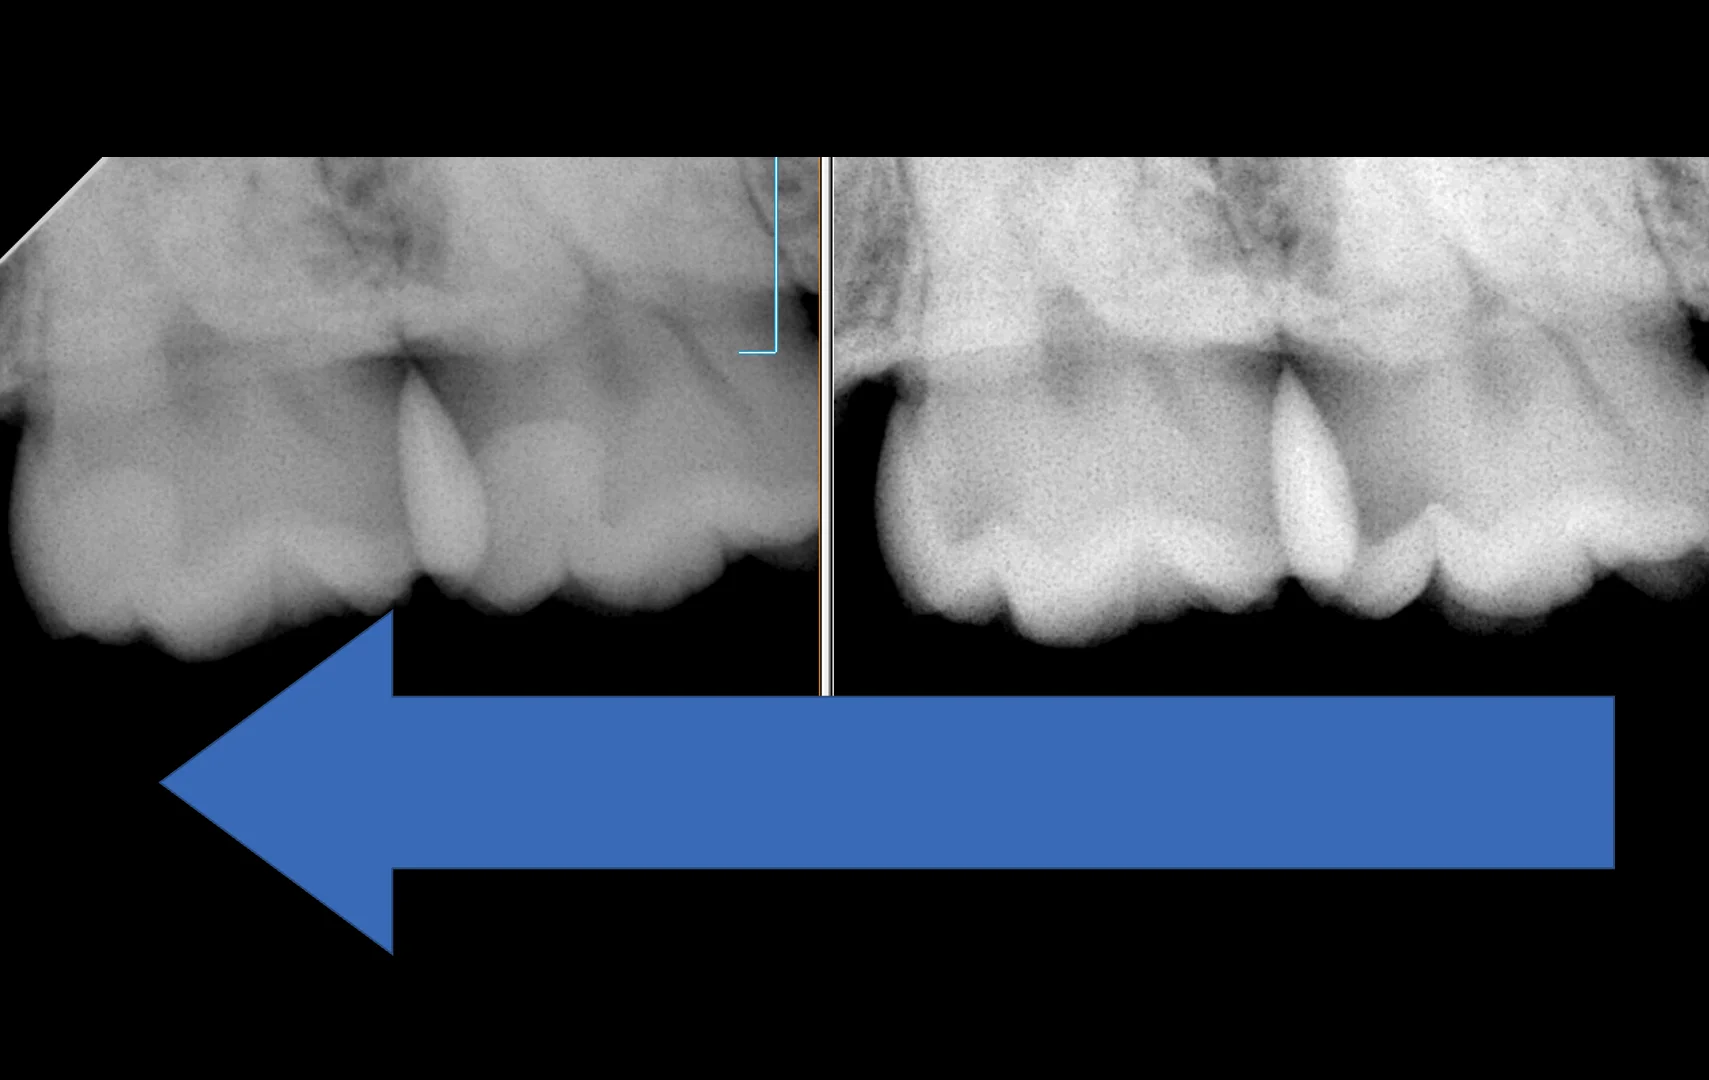

レントゲンの術前術後はこちらになります。

左側のレントゲンで見てもらうとわかるのですが、白く写っているところが今回治療した部位になります。

こう見ると、左の歯が1/4ほど、右の歯が1/3ほど歯を失っているのがわかるかと思います。

再度、虫歯を取り切ったところの写真を見てもらうとどれだけ歯を温存できているのかがイメージとしてつきやすいかもしれませんね。